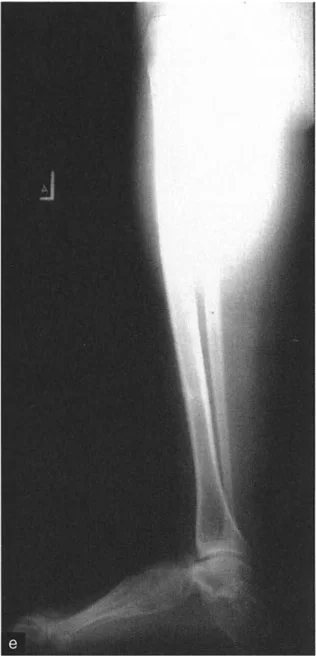

* الأشعة السينية (X-rays) الواقفة لكامل الطرف السفلي: هذه الأشعة ضرورية لتقييم المحاذاة الكلية للطرف السفلي تحت تأثير وزن الجسم. يطلب الأستاذ الدكتور محمد هطيف صورًا شعاعية كاملة الطول للساق أثناء الوقوف (Full-length standing alignment films) لتقييم المحور الميكانيكي للساق وتحديد زوايا المفاصل بدقة.

* الأشعة السينية الجانبية والامامية الخلفية للكاحل: تُظهر هذه الصور تفاصيل مفصل الكاحل نفسه، بما في ذلك زاوية القصبة الأمامية البعيدة (ADTA) وزاوية القصبة الوحشية البعيدة (LDTA)، وهي زوايا حاسمة لتحديد التشوه في المستويين الأمامي والسهمي.

* رسم المحاور الميكانيكية والتشريحية: لتحديد نقطة مركز دوران التشوه (CORA)، وهي النقطة التي يجب أن تتم عندها الجراحة لتصحيح التشوه بأقل قدر من المضاعفات.

جراحة قطع العظم فوق الكاحل (SMO) هي الإجراء الأكثر شيوعًا لتصحيح تشوهات قصبة الساق البعيدة. تتضمن هذه الجراحة قطعًا دقيقًا في عظم الساق (القصبة) فوق مفصل الكاحل مباشرة، ثم إعادة محاذاة العظم وتثبيته في الوضع الصحيح. هناك عدة أنواع من هذه الجراحة: